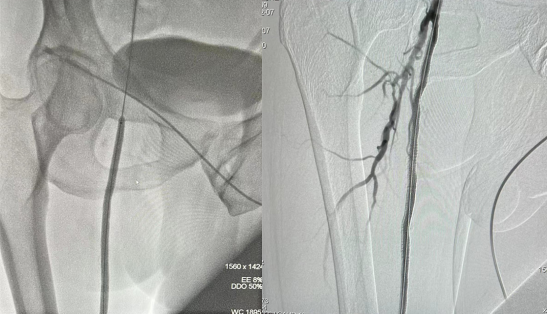

经康复医学科、医学影像中心等多科室讨论,并与患者及家属充分沟通征得同意,2月7 日下午14:00在上级专家指导下行右下肢动脉造影加血管成形术的介入治疗。术中开通闭塞段血管逐段行球囊扩张,并置入两枚动脉血管支架。术后造影右下肢血流畅通,患者症状亦明显改善。